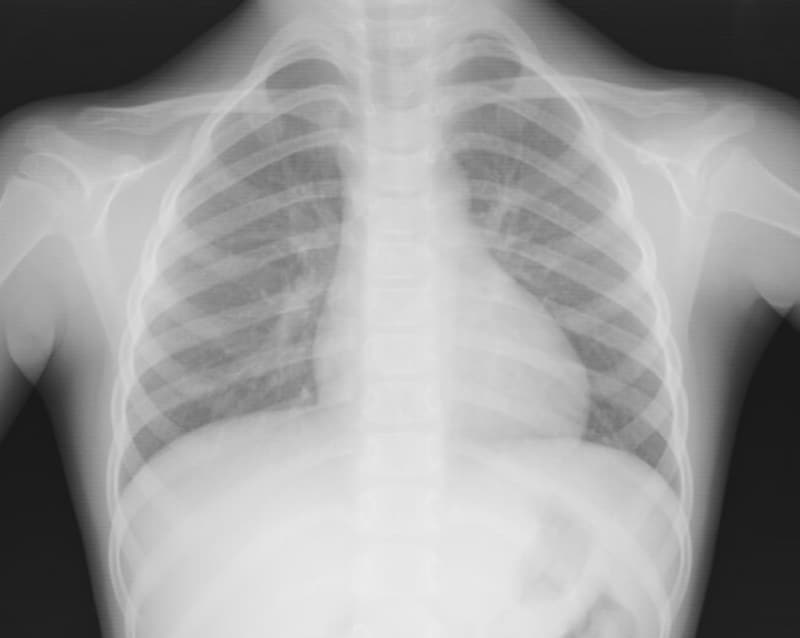

![]() |

| 胸部のX写真。肺や心臓の状態をチェックします |

- X線検査

膠原病の場合は、様々な臓器に炎症を起こります。咳がひどい場合は、胸部X線、腹痛なら腹部X線が必要になります。造影剤を使った検査も必要になります。クローン病や潰瘍性大腸炎では、造影剤を肛門から入れて検査する注腸造影検査を行います - 超音波検査